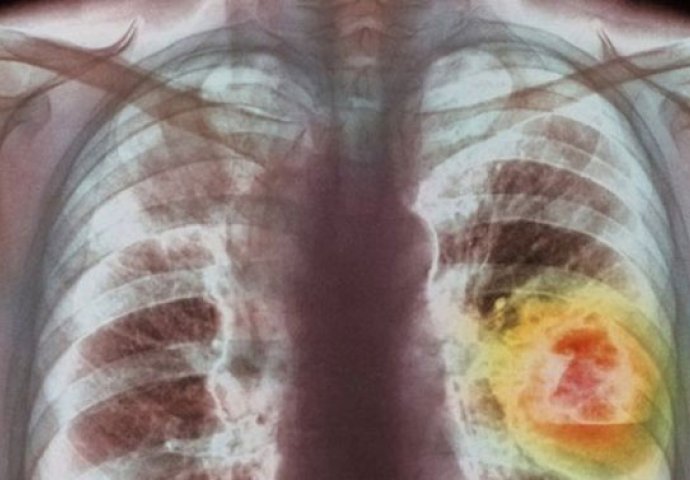

karcinom